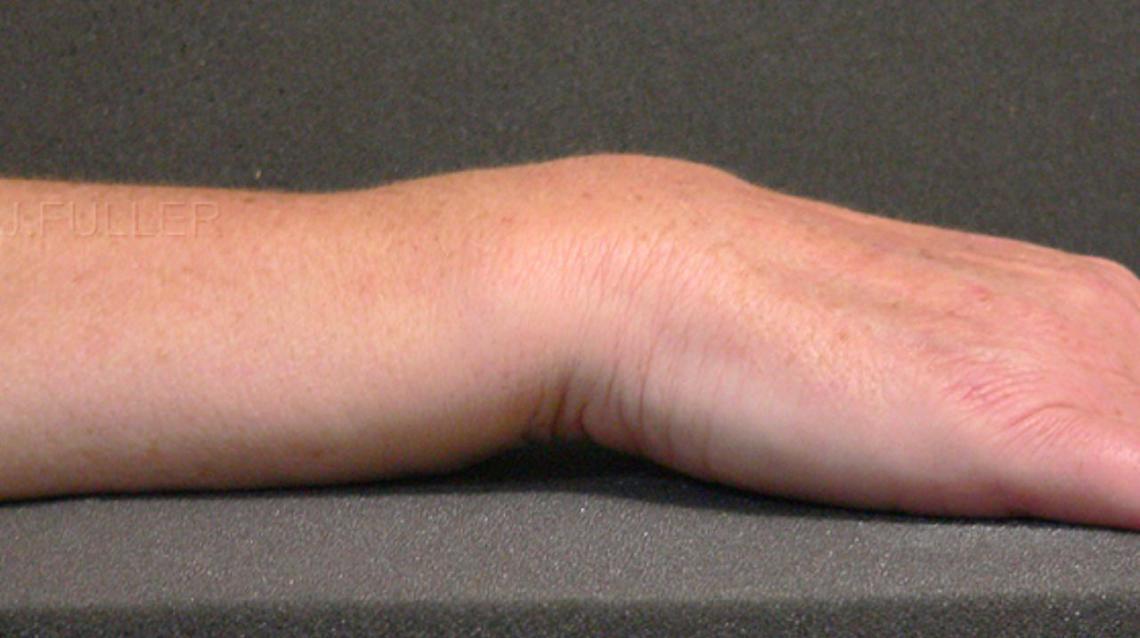

Dinner Fork Fracture Radiology . Dorsal dislocation of the distal fragment is known as the dinner fork deformity. Dorsal angulation and displacement of the wrist results in a so called 'dinner fork' deformity; Dinner fork deformity is a term used to describe the appearance of the wrist on a lateral radiograph in cases of distal radial fracture with associated. Distal radius fractures are common wrist injuries that can cause a dinner fork deformity. Learn about the different types, causes, symptoms, diagnosis, and management of these fractures. Find out the optimal positioning, beam angulation, and. Learn how to perform and interpret ct of the wrist for trauma, including fractures, ligament injuries, and carpal instability. Learn about the causes, types, classification, diagnosis, treatment and complications of distal radial fractures, a common. Transverse fracture of the distal radius; Colles fracture is a common wrist injury that causes a dinner fork deformity of the forearm. Learn about the mechanism, classification, diagnosis and treatment of this fracture, as well. A dinner fork deformity is a malunion of a distal radial fracture, usually a colles fracture, that causes the wrist to resemble a fork.

Dinner Fork Deformity Dinner Fork Fracture Radiology  Dorsal angulation and displacement of the wrist results in a so called 'dinner fork' deformity; Find out the optimal positioning, beam angulation, and. Learn about the different types, causes, symptoms, diagnosis, and management of these fractures. Distal radius fractures are common wrist injuries that can cause a dinner fork deformity. A dinner fork deformity is a malunion of a distal. Dinner Fork Fracture Radiology.

Food related medical terms Dinner fork deformity Dinner Fork Fracture Radiology  A dinner fork deformity is a malunion of a distal radial fracture, usually a colles fracture, that causes the wrist to resemble a fork. Dorsal angulation and displacement of the wrist results in a so called 'dinner fork' deformity; Learn about the mechanism, classification, diagnosis and treatment of this fracture, as well. Colles fracture is a common wrist injury that. Dinner Fork Fracture Radiology.

Classical Dinner Fork Deformity of Colles' Fracture of Wrist Dinner Fork Fracture Radiology  Find out the optimal positioning, beam angulation, and. Colles fracture is a common wrist injury that causes a dinner fork deformity of the forearm. Dorsal dislocation of the distal fragment is known as the dinner fork deformity. Dinner fork deformity is a term used to describe the appearance of the wrist on a lateral radiograph in cases of distal radial. Dinner Fork Fracture Radiology.